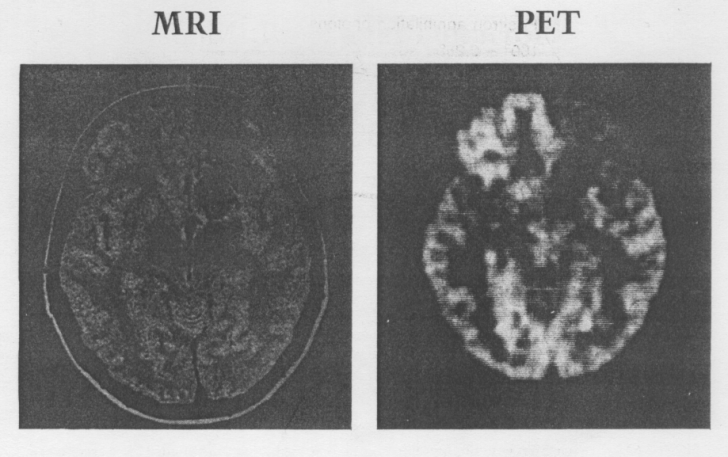

Tomografia computerizata cu emisie de pozitroni (PET)

Tomografia computerizata cu emisie de pozitroni (PET) Posibilitatea investigatiilor imagistice cu ajutorul emisiei de fotoni de `nalt energie produsi prin anihilarea pozitronilor emisi de anumiti izotopi a fost demonstrat de aproapeCiteste tot ... 678 cuvinte

Dimensiune mica + cu imagini |